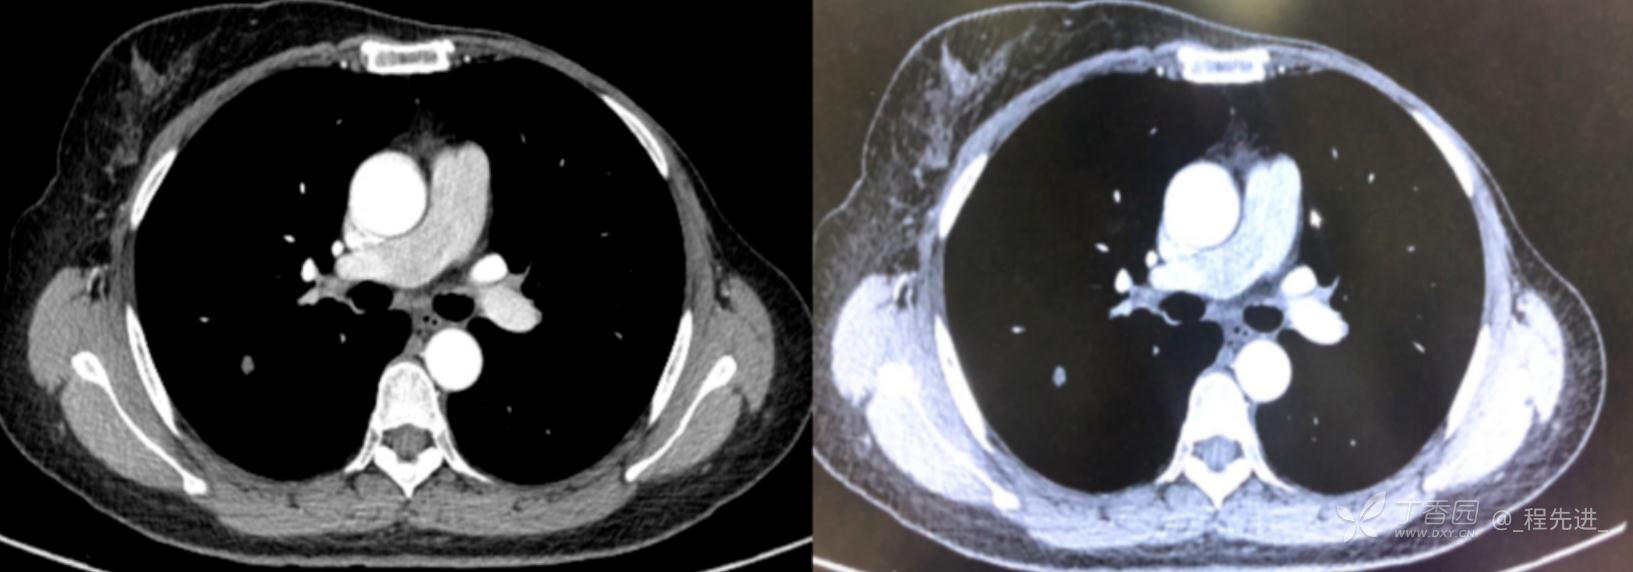

患者性别:女

患者年龄:52岁

简要病史:体检发现右肺上叶结节

既往史:左乳腺癌术后,化疗后